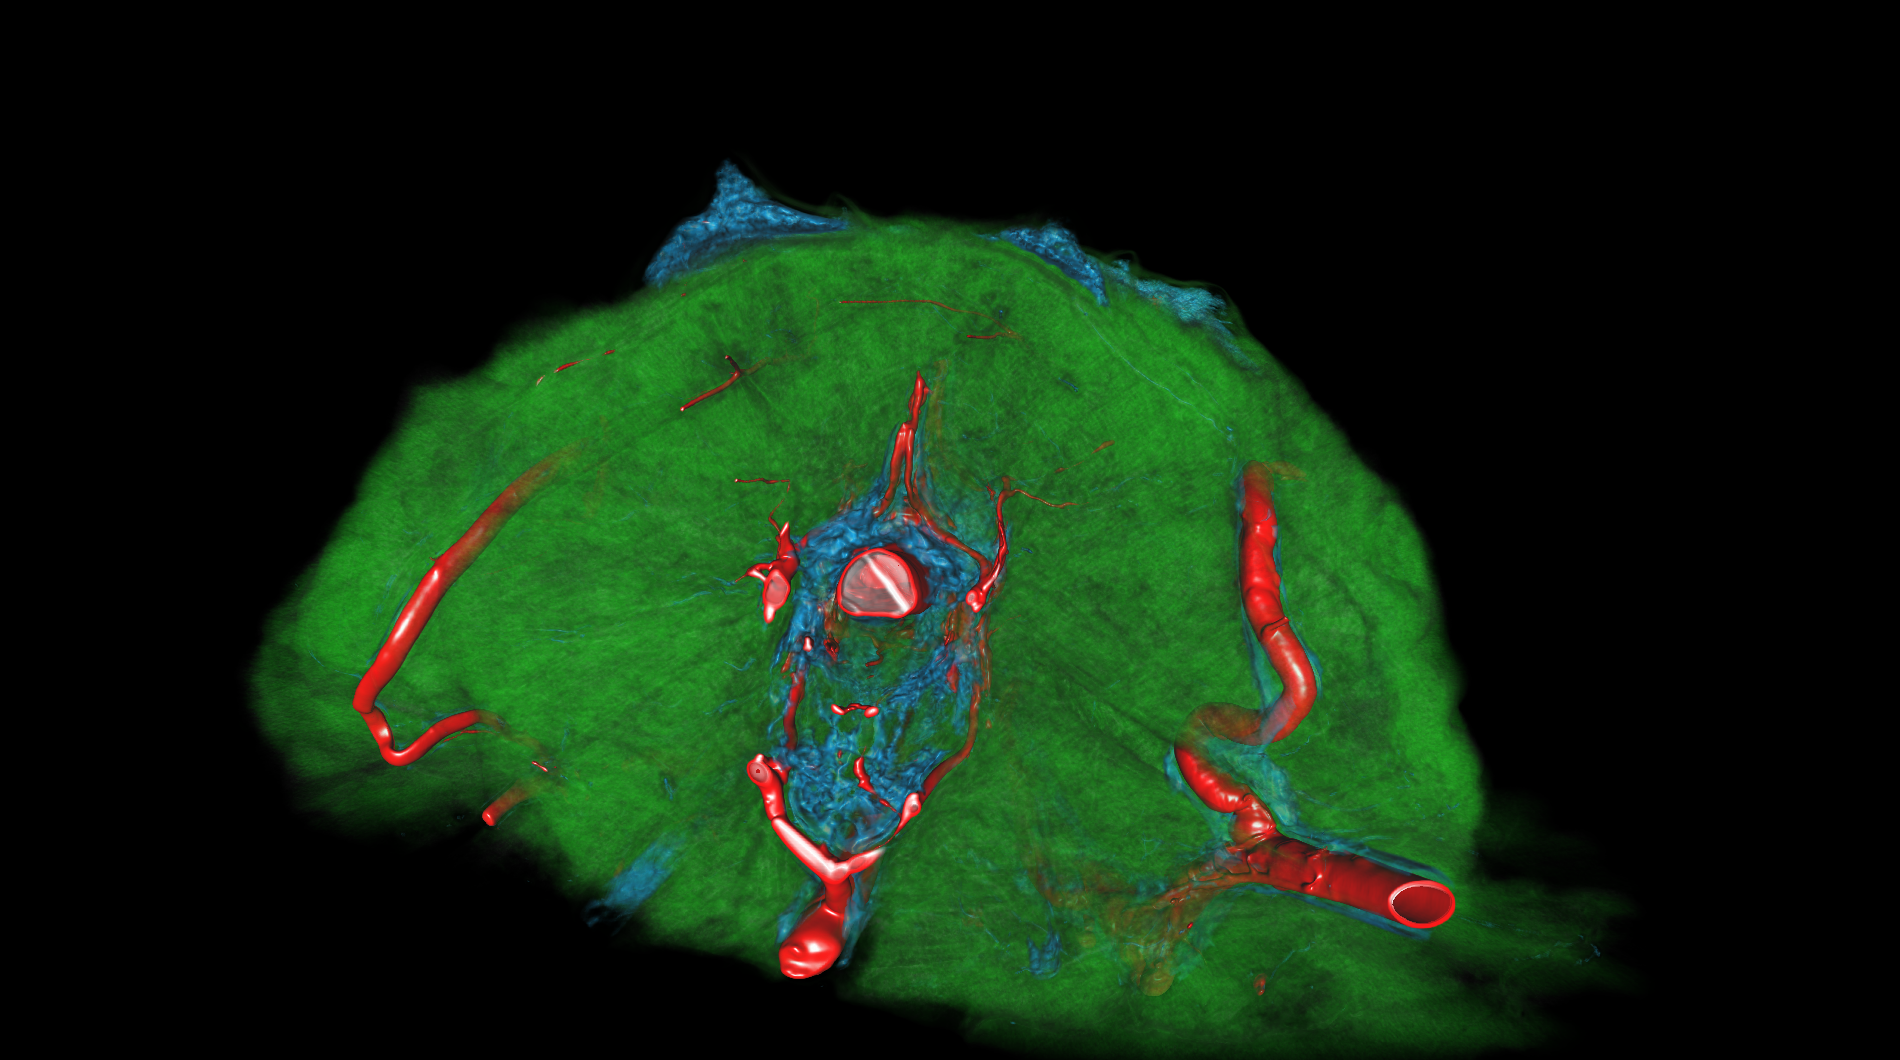

| The medical-04 workload evaluates medical visualization techniques using the Tuvok library and OpenGL API. It features slice rendering and raycasting with 1D and 2D transfer functions, exploring datasets from a beating heart, brain, and alligator. Clipping planes and varying voxel densities test performance in medical imaging workflows, simulating scenarios like MRI and CT analysis. | |||

| Composite Score: | 271.71 | ||

| Graphics Renderer: | RTX 6000 Ada Generation | ||

| Index | Description | Weight | Result (FPS) |

| 1 |

Slice beating heart with 1D transfer

Slice beating heart with 1D transfer

|

10.00 |

906.30

|

| 2 |

Raycasting of a beating heart with 1D transfer

Raycasting of a beating heart with 1D transfer

|

10.00 |

1784.91

|